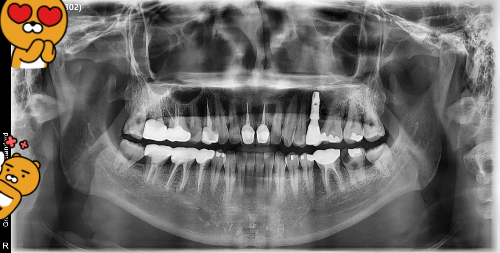

저는 이제 40을 채워가는 나이인데요. 벌써 임플란트가 3개나 있습니다. ㅠㅠ 여러분들은 몇개나 있나요? 오복 중 하나라고 일컫는 치아건강. 아무래도 저는 평생 치과를 다녀야할 운명인 듯 합니다. 중학생때부터 다니기 시작한 치과인데요. "위잉~" 하는 날카로운 기계 소리, 코끝을 찌르는 특유의 소독약 냄새. 치과는 어른이 되어서도 가기 싫은 장소 1위로 꼽힙니다. 치료 과정의 통증도 공포스럽지만, 사실 더 무서운 건 계산대 앞에 섰을 때 마주할 진료비 영수증입니다. 하지만 양치질을 아무리 꼼꼼히 해도 혀끝으로 아랫니 안쪽을 훑어보면 까끌까끌한 돌 같은 이물감이 느껴질 때가 있습니다. 바로 세균 덩어리가 굳어진 '치석'입니다. 이걸 "양치질 더 열심히 하면 없어지겠지"라고 방치하다가는 잇몸 뼈가 녹아내려 결국 수백만 원짜리 임플란트 시술을 받아야 하는 대참사가 벌어집니다. 오늘은 커피 몇 잔 값으로 내 치아 수명을 10년 더 늘릴 수 있는 확실한 '국가 혜택'과, 스케일링을 둘러싼 억울한 오해들을 속 시원하게 풀어드립니다.